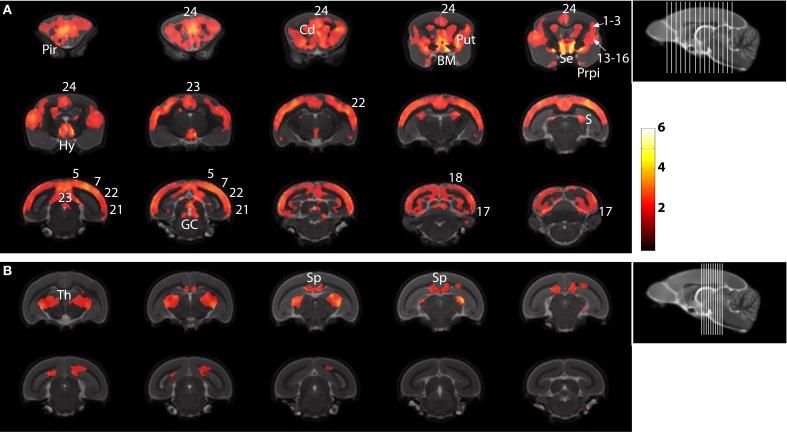

Cerebral atrophy is one of the most widely brain alterations associated to aging. A clear relationship has been established between age-associated cognitive impairments and cerebral atrophy. The mouse lemur (Microcebus murinus) is a small primate used as a model of age-related neurodegenerative processes. It is the first non-human primate in which cerebral atrophy has been correlated with cognitive deficits. Previous studies of cerebral atrophy in this model were based on time consuming manual delineation or measurement of selected brain regions from magnetic resonance images (MRI). These measures could not be used to analyse regions that cannot be easily outlined such as the nucleus basalis of Meynert or the subiculum. In humans, morphometric assessment of structural changes with age is generally performed with automated procedures such as voxel-based morphometry (VBM). The objective of our work was to perform user-independent assessment of age-related morphological changes in the whole brain of large mouse lemur populations thanks to VBM. The study was based on the SPMMouse toolbox of SPM 8 and involved thirty mouse lemurs aged from 1.9 to 11.3 years. The automatic method revealed for the first time atrophy in regions where manual delineation is prohibitive (nucleus basalis of Meynert, subiculum, prepiriform cortex, Brodmann areas 13-16, hypothalamus, putamen, thalamus, corpus callosum). Some of these regions are described as particularly sensitive to age-associated alterations in humans. The method revealed also age-associated atrophy in cortical regions (cingulate, occipital, parietal), nucleus septalis, and the caudate. Manual measures performed in some of these regions were in good agreement with results from automatic measures. The templates generated in this study as well as the toolbox for SPM8 can be downloaded. These tools will be valuable for future evaluation of various treatments that are tested to modulate cerebral aging in lemurs.

脑萎缩是与衰老相关的最广泛的大脑改变之一。年龄相关的认知障碍与脑萎缩之间存在明确的关系。鼠狐猴(Microcebus murinus)是一种小型灵长类动物,被用作与年龄相关的神经退行性过程的模型。它是第一个与认知缺陷相关的非人类灵长类动物。以前对这种模型的脑萎缩的研究是基于磁共振成像(MRI)的手动勾画或测量选定脑区。这些措施不能用于分析那些不能轻易勾勒出的区域,如梅尼埃基底核或下托。在人类中,形态测量学评估与年龄相关的结构变化通常采用基于体素的形态测量学(VBM)等自动程序进行。我们的工作目标是通过 VBM 对大型鼠狐猴种群的整个大脑进行与年龄相关的形态变化的用户独立评估。该研究基于 SPM8 的 SPMMouse 工具箱,涉及 30 只年龄在 1.9 至 11.3 岁之间的鼠狐猴。该自动方法首次揭示了在手动勾画受限的区域(梅尼埃基底核、下托、梨状皮层、Brodmann 区域 13-16、下丘脑、壳核、丘脑、胼胝体)出现萎缩。其中一些区域被描述为对人类与年龄相关的改变特别敏感。该方法还揭示了皮质区域(扣带回、枕叶、顶叶)、隔核和尾状核与年龄相关的萎缩。在这些区域中的一些区域中进行的手动测量与自动测量的结果非常吻合。本研究中生成的模板以及用于 SPM8 的工具箱均可下载。这些工具对于未来评估各种治疗方法非常有价值,这些方法被测试用于调节灵长类动物的大脑衰老。